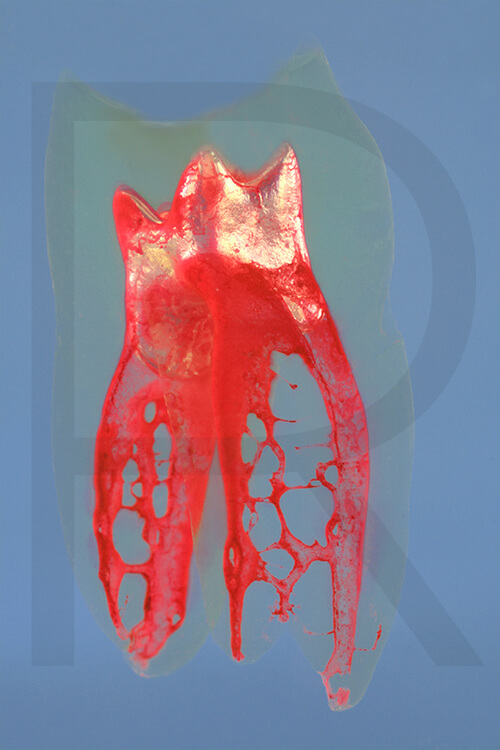

Bildauswahl mit schwebender Aufhängung

- Foto hinter 3mm Acrylglas, rahmenlos

- hochwertige, unsichtbare Aufhängung, "schwebend“

- Hoher UV-Schutz für lang anhaltend strahlende Farben

- Bruchsicher und leichter als Glas

- Beeindruckende Farben und brilliante Tiefenwirkung

- Druck erfolgt ohne Wasserzeichen

- Bildgröße Bild 7: 90 x 90 cm, quadratisch

- Preis: auf Anfrage, zuzüglich 20,90 Euro Versand & Porto innerhalb Deutschlands, weiterer Versand auf Anfrage

- Bildgröße Bild 8: 90 x 60 cm, Hochformat

Preis: 490,00 Euro, zuzüglich 16,90 Euro Versand & Porto innerhalb Deutschlands, weiterer Versand auf Anfrage

Wenn Sie Interesse an den Fotos transparenter Zahnpräparate haben, bieten wir hier die Möglichkeit einige Versionen als Acrylbilder (alle Detailinformationen zu Größe und Preis siehe obige Auswahl) zu bestellen.

Die Bilder sind nicht nur zur Praxisverschönerung geeignet sondern auch eine wertvolle Unterstützung bei der Patientenberatung vor endodontischen Behandlungen.